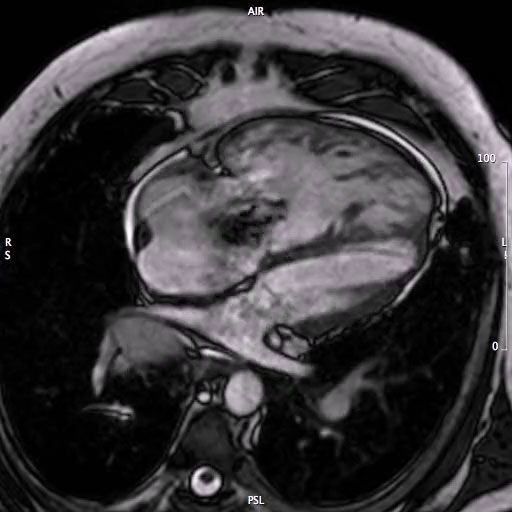

La Risonanza Magnetica nella diagnosi differenziale dell’ipertrofia nell’atleta.

Argomento principale: Medicina dello sport